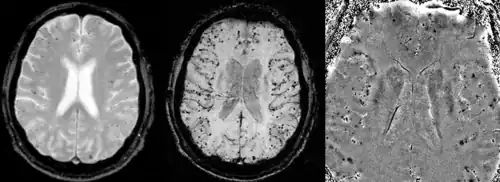

A AAC só pode ser definitivamente diagnosticada por uma autópsia (post-mortem).[25] As biópsias podem desempenhar um papel no diagnóstico de casos prováveis.[26] Quando não há tecido disponível para biópsia, os critérios de Boston são usados para determinar casos prováveis de AAC a partir de dados de ressonância magnética ou tomografia computadorizada. Os critérios de Boston exigem evidências de múltiplas hemorragias lobares ou corticais para rotular um paciente como provavelmente portador de AAC.[25] A imagem ponderada por suscetibilidade foi proposta como uma ferramenta para identificar microhemorragias relacionadas à AAC.[27]

Exames de imagem

A angiopatia amiloide cerebral pode se apresentar com hemorragia intracerebral lobar ou micro sangramentos no cérebro. O sangramento geralmente ocorre nas superfícies do cérebro, em contraste com a hemorragia intracraniana devido à pressão arterial elevada que ocorre em locais profundos do cérebro, como os gânglios basais e a ponte. No sangramento intracerebral lobar, a tomografia computadorizada (TC) mostraria uma área de hemorragia hiperdensa e um odema hipodenso ao redor do local da hemorragia.[17]

A sequência de RM de eco de gradiente e a imagem ponderada por suscetibilidade (SWI) são úteis na detecção de micro sangramentos e deposição de ferro no córtex cerebral (siderose superficial cortical).[17] Outros indicadores de RM de AAC incluem hiperintensidades de substância branca e afinamento cortical.[28]